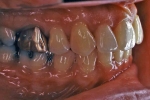

マルチブラケット終了時